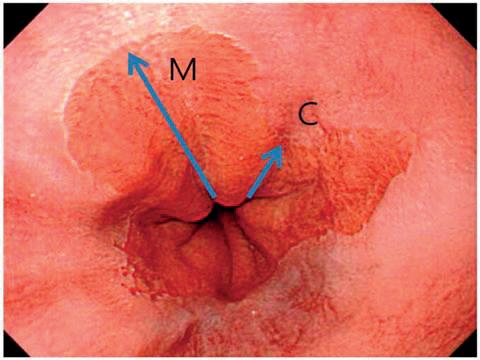

Endoskopisk gjenkjennes forandringene enkelt, siden sylinderepitel har en mer rosa-rød farge sammenliknet med hvitlig plateepitel (figur 2). Sees sylinderepitel i øsofagus, det vil si proksimalt for der ventrikkefoldene starter, kalles det BØ; gitt at utbredelsen er på minst 1 cm i spiserørets lengde og biopsi bekrefter intestinal metaplasi. En endoskopibeskrivelse bør angi utbredelsen av de sammenhengende sirkumferensielle forandringene fra øvre ventrikkelfold, samt den maksimale utbredelsen inkludert eventuelle ikke-sirkumferensielle utløpere. Dette er den såkalte Praha-klassifikasjonen (figur 2), der eksempelvis forandringer på 4 cm i sirkumferens med et tillegg av en utløper på 2 cm vil bli angitt som C4M6, der C angir sirkumferens og M angir maksimum. Slimhinne inspiseres deretter nøye etter fokale lesjoner. Slike lesjoner kommer tydeligere frem ved applikasjon av 2% mateddik på slimhinnen og/ eller ved bruk av innebygde lysfilterfunksjoner i gastroskopet (“Narrow Band Imaging”), slik at man da kan gjøre en fokusert biopsering.

Figur 2. - Barretts øsofagus. Dette endoskopiske bildet viser nedre del av spiserøret mot overgang til magesekk der nederste del av dekket av Barretts slimhinne. Utbredelsen av Barretts slimhinne angis i henhold til Prahaklassifikasjonen med lengden på de kontinuerlige sirkumferensielle (C) og de maksimale (M) forandringene.

Figur 1. CM klassifikasjon av Barretts øsofagus Endoskopisk gjenkjennes forandringene enkelt, siden sylinderepitel har en mer rosa-rød farge sammenliknet med hvitlig plateepitel.